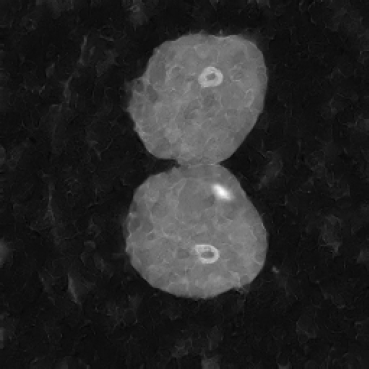

As shown in Figure 5, the generated slices exhibit high consistency across adjacent slices. The anatomical structures and semantic patterns are smoothly and coherently preserved between slices, indicating that our model is capable of generating 3D-consistent synthetic images rather than isolated 2D slices.